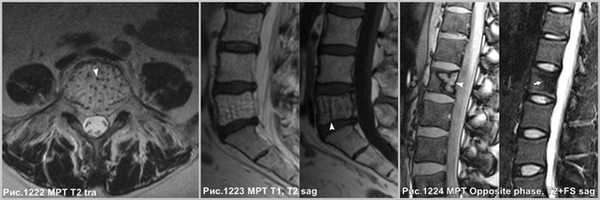

Крупная гемангиома в теле L5 позвонка, распространяющаяся на всё его тело, приводящая к перестройке губчатого вещества кости, с разряжением губчатого вещества и наличием вертикальных утолщенных костных балок (головки стрелок на рис.1222,1223). Гемангиома в теле позвонка, имеющая жировую интенсивность МР-сигнала - ↑сигнал по Т1, с обозначением контура на последовательности в противофазе (головка стрелки на рис.1224), и имеющая выпадение МР-сигнала в режиме Т2 с жироподавлением (стрелка на рис.1224), что соответствует жировой ткани в гемангиоме.

Гипертрофированные вертикальные балки губчатого вещества превосходно видны на КТ (рис.1227 и головки стрелок на рис.1225,1226).